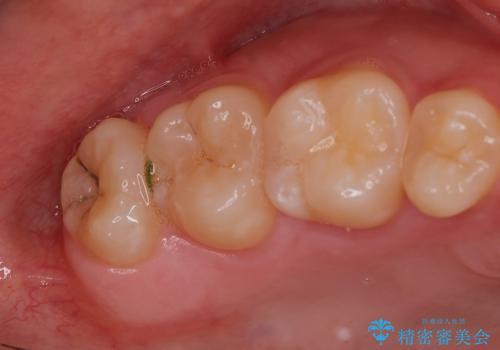

- 親知らずのところが痛く抜きたいとの事で来院。

しっかり麻酔が効いているのを確認して抜歯を行いました。

処置は当日行う事が可能です。